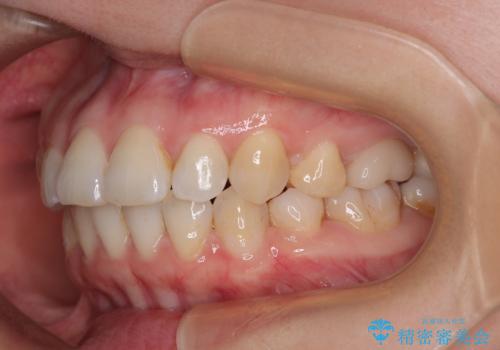

インビザライン・モデレートは、製作できるアライナーの枚数に制限があるため、移動可能な量に限りがあるものの、インビザライン・ライトよりも枚数が多いため、幅広い症例に対応可能です。